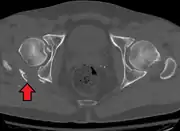

Gallery

Axial CT image (viewed on bone windows) of a complex comminuted left acetabular fracture involving both anterior and posterior columns.